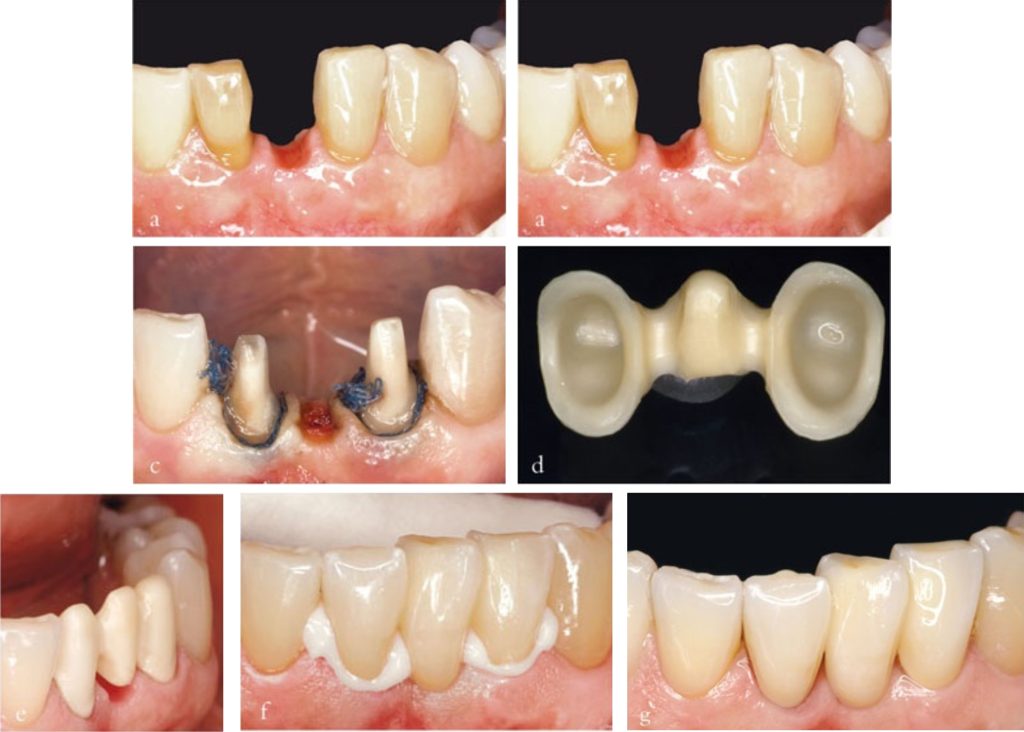

Mão toàn sứ có độ bền kém hơn so với mão sứ – kim loại. Khi dùng làm răng trụ cho cầu răng, chúng chỉ được chỉ định cho cầu ba đơn vị trong những trường hợp yêu cầu thẩm mỹ cao. Trong những trường hợp này, nên sử dụng cấu trúc sườn zirconia (Hình 3-7).